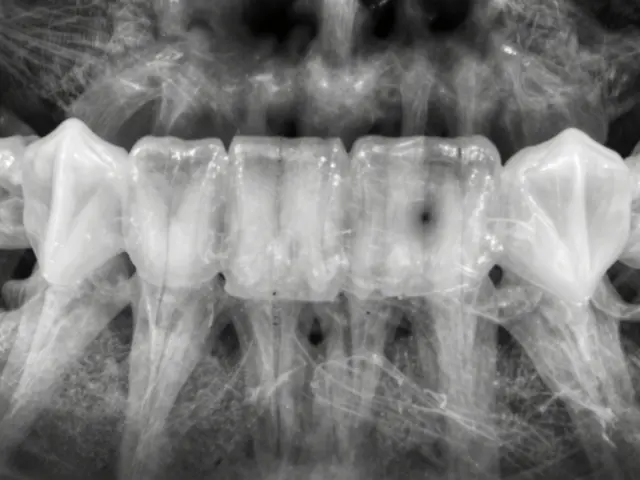

Existují různé druhy zubních protéz a každý je určen pro konkrétní situaci, buďto dodat chybějící zuby nebo celkově nahradit všechny zuby v ústech. Například mosty a korunky jsou protézy, které jsou připevněny na existující zuby nebo na implantátech. Díky tomu jsou stabilní a nepohybují se v ústech, což je pro mnohé pacienty výhodou. Na druhou stranu máme pak snímatelné protézy, které můžeme vyndat z úst, když je to potřeba - před spaním, o jídle nebo když je třeba čistit.

Možná se ptáte, kdy v životě přichází bod, kdy je potřeba zubní protéza? Odpověď na to záleží na několika faktorech. Mnozí z nás by si mohli myslet, že protézy jsou určeny pouze pro starší lidi, kteří ztratili všechny své zuby. Ale skutečnost je taková, že i mladí lidé mohou potřebovat zubní protézu z důvodů jako je úraz, choroba nebo zkušenost s velkým rozsahem zubního kazu.